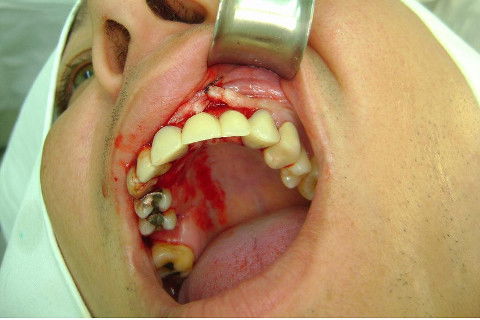

Cirurgia realizada hoje de manhã...No planejamento percebi medindo espessura do rebordo com especímetro que as medidas não estavam muito boas, ou o ideal, em torno de 4,5 a 5 mm ate´o terço médio do rebordo e melhorava no final, com 6 a 7 mm. Optei então por uma pequena expansão usando os expansores rosqueáveis. Aconteceu uma pequena fenestração na hora da fixação dos implantes, especialmente na região do 22 que fraturou o início da tábua óssea, mas não me preocupei porque não foi mais do que 2 mm de fratura em direção apical, o implante ficou infraósseo e com boa estabilidade (60 N no 21 e 40 N no 22). Esta fratura tb não deixou osso completamente solto, foi do tipo galho verde, deixei em posição e suturei normalmente. Só não fiz e nem estava planejado carga imediata mesmo, mais pelo motivo da oclusão inadequada do caso.

Fotos do caso